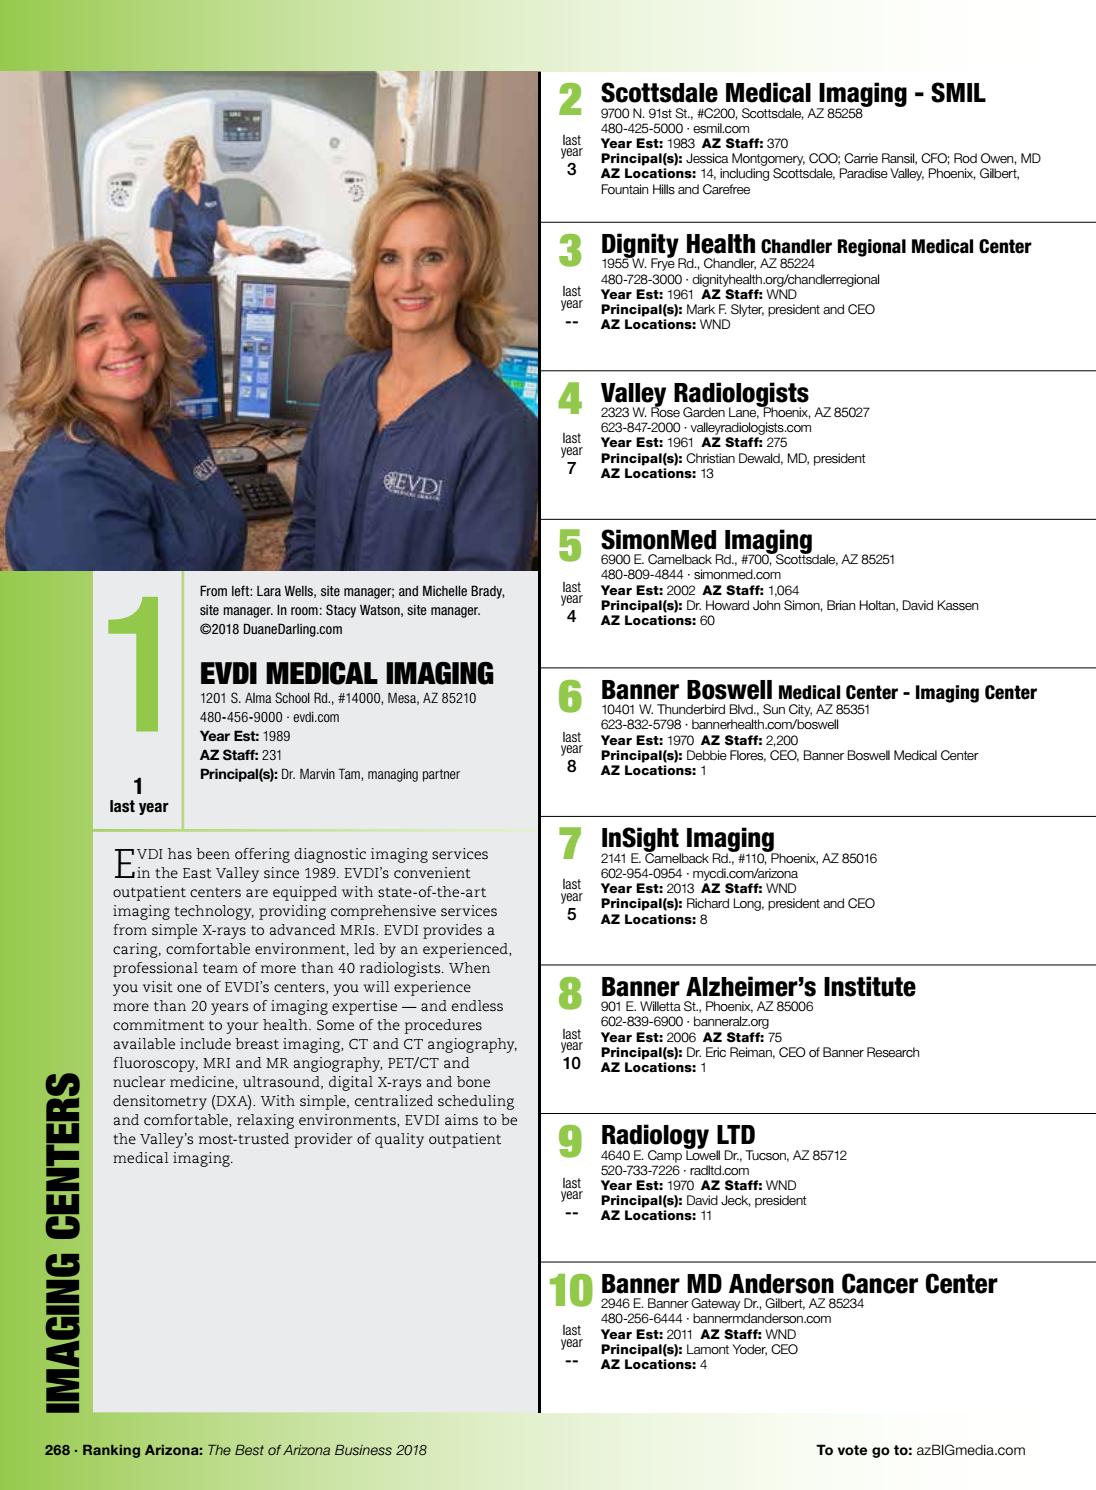

Ranking Arizona 2018 Digital Issue By Az Big Media Issuu